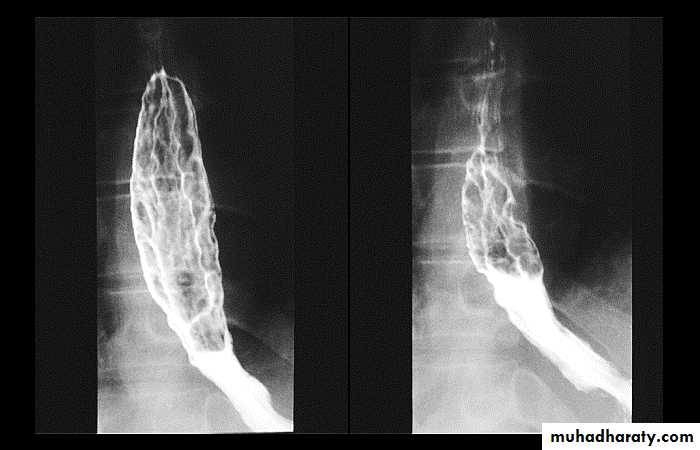

Esophageal Varieces

Dilatation of venous plexus in the wall of the esophagus due to increased pressure ( portal H.T.).Important cause of Hematemesis .

Early changes seen in the mucosa (D.C.) loss of parallelism with thick and tortuous folds.

Later multiple small filling defects (fine cobble stone).

In advanced stage large filling defects ( coarse cobble stone ) .

7More advanced stage elongated and worm like filling defect .

The changes are seen at lower third and gastric fundus.